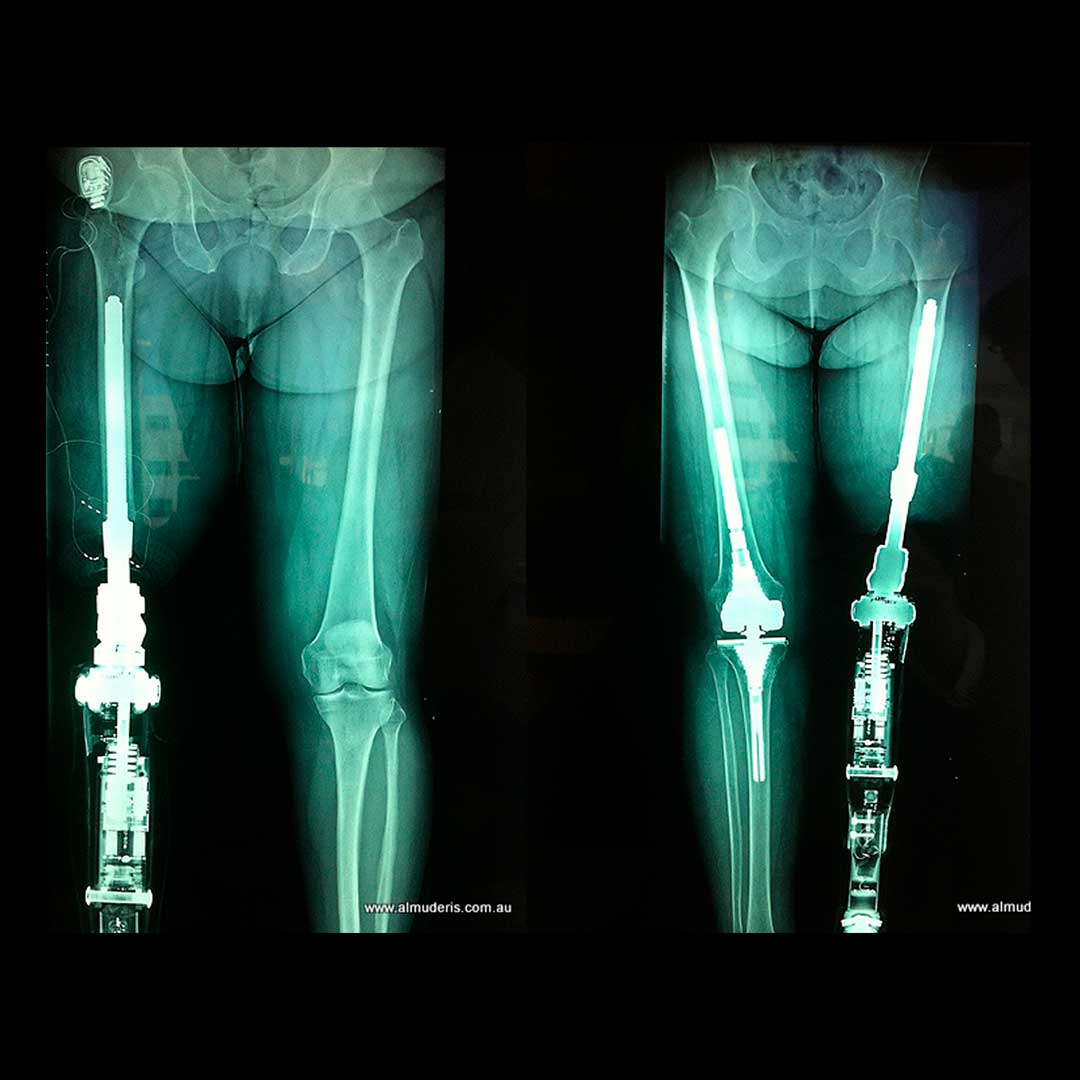

Osseointegration involves inserting a prosthetic implant into the residual bone of an amputee to which an external prosthesis can be directly attached, eliminating the need for a traditional socket-mounted prosthesis. This cutting-edge surgery is revolutionising limb reconstruction and allowing robotic components to meld directly with the skeletal system. Although most widely seen in lower limb amputees, OI has recently been applied to upper limb and even digital reconstruction with great effect. The osseointegration group of Australia is leading the way forward with this ground-breaking technology and surgical technique. OI is the future of limb prosthesis, watch this space!

Image source: www.almuderis.com.au